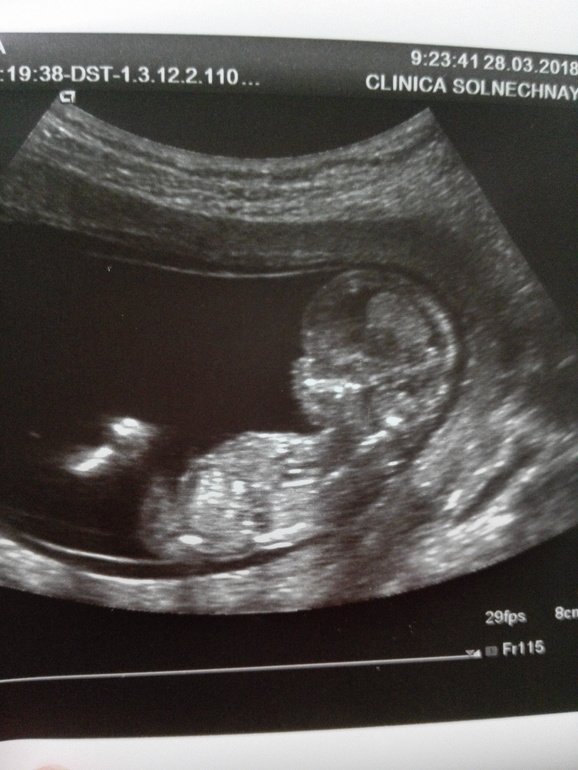

На третьем УЗИ при беременности можно узнать пол ребёнка, так как на сроке 19-21 неделя конечности хорошо визуализируются. Иногда малыш принимает закрытую позу, не давая определить половую принадлежность. В этом случае будущим родителям остаётся ждать следующей плановой процедуры.

Современная аппаратура дает возможность узнать на УЗИ беременности пол ребенка в начале второго семестра. Единственное условие — малыш должен располагаться в удачной проекции.

Обязательное второе УЗИ делают 19-24 неделе беременности трансабдоминально.

Пол ребенка можно уже определить точно, как и рассмотреть при скрининге улыбку и ямочки на щеках.